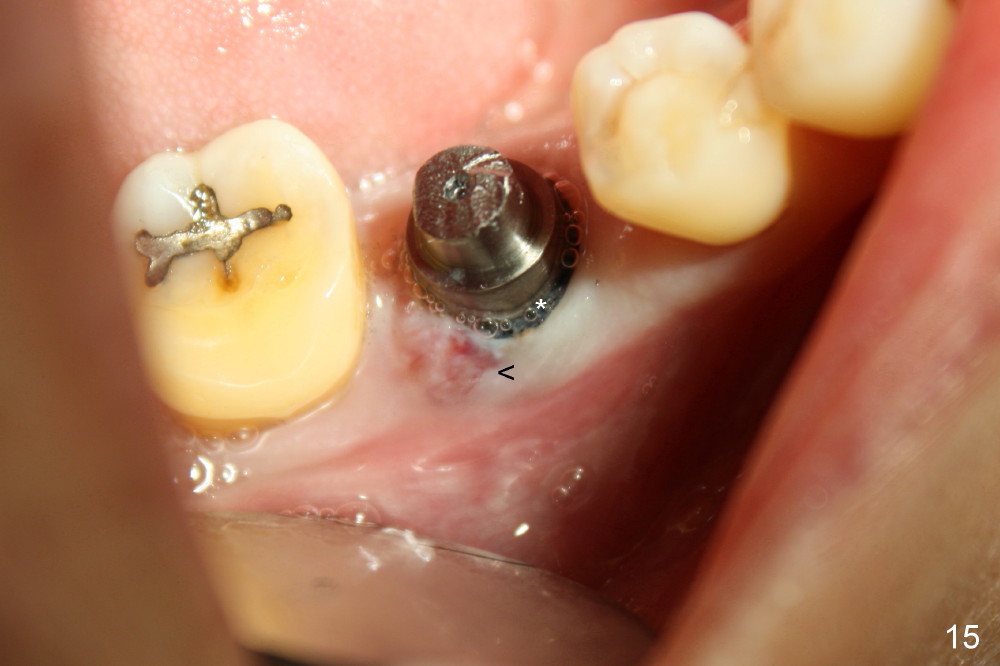

The implant is stable with sign of apparent bone growth around it 4.5 months postop (Fig.14). There is painless localized gingival erythema and edema (Fig.15 <). The infection is most likely from a fistula of #9 (perio-endo disease, after perio surgery and RCT). Without too much thought, an unipost has been cemented, gingival retraction cord (*) inserted and impression taken.